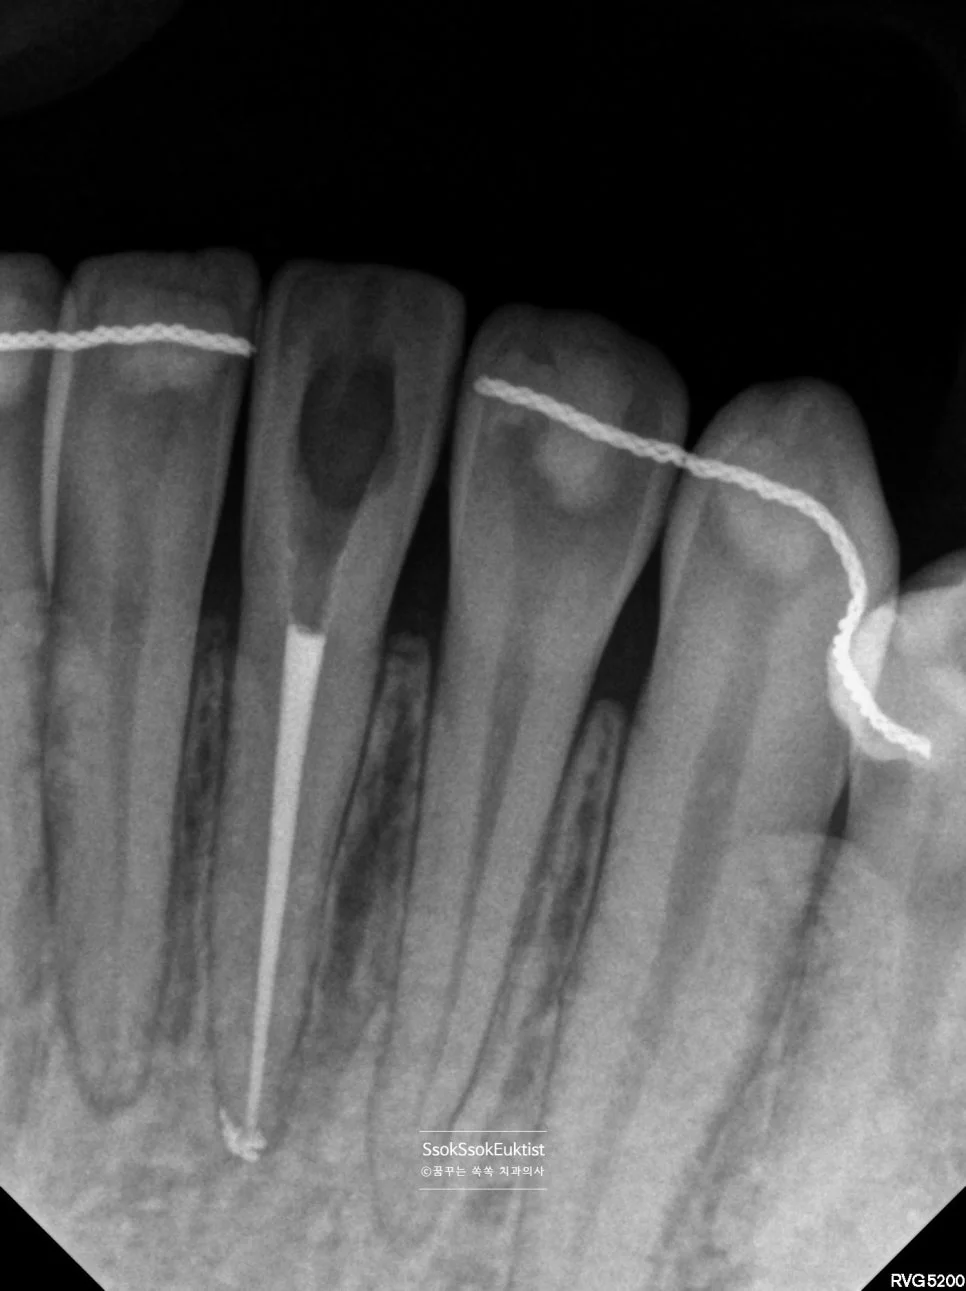

신경치료 완료 X-ray — 신경관 끝까지 가득 채워진 모습

신경관 끝까지 가득 채워진 것 같다면 잘 된 신경치료입니다^^ 실활치 미백을 한 후 모습은 어떨까요?

최소 1주 정도의 시간이 지난 후 신경치료를 위해 형성한 hole을 레진으로 매우면 치료가 종결됩니다.

최종 결과 — 레진 충전까지 완료, 어느 치아를 치료했는지 모를 정도로 자연스러운 모습

어떤가요?^^ 어느 치아를 치료했는지도 모를 정도로 원래의 색으로 돌아왔습니다. 박수 박수!!

치료 완료 후 파노라마 X-ray — 신경치료 부위 최종 확인